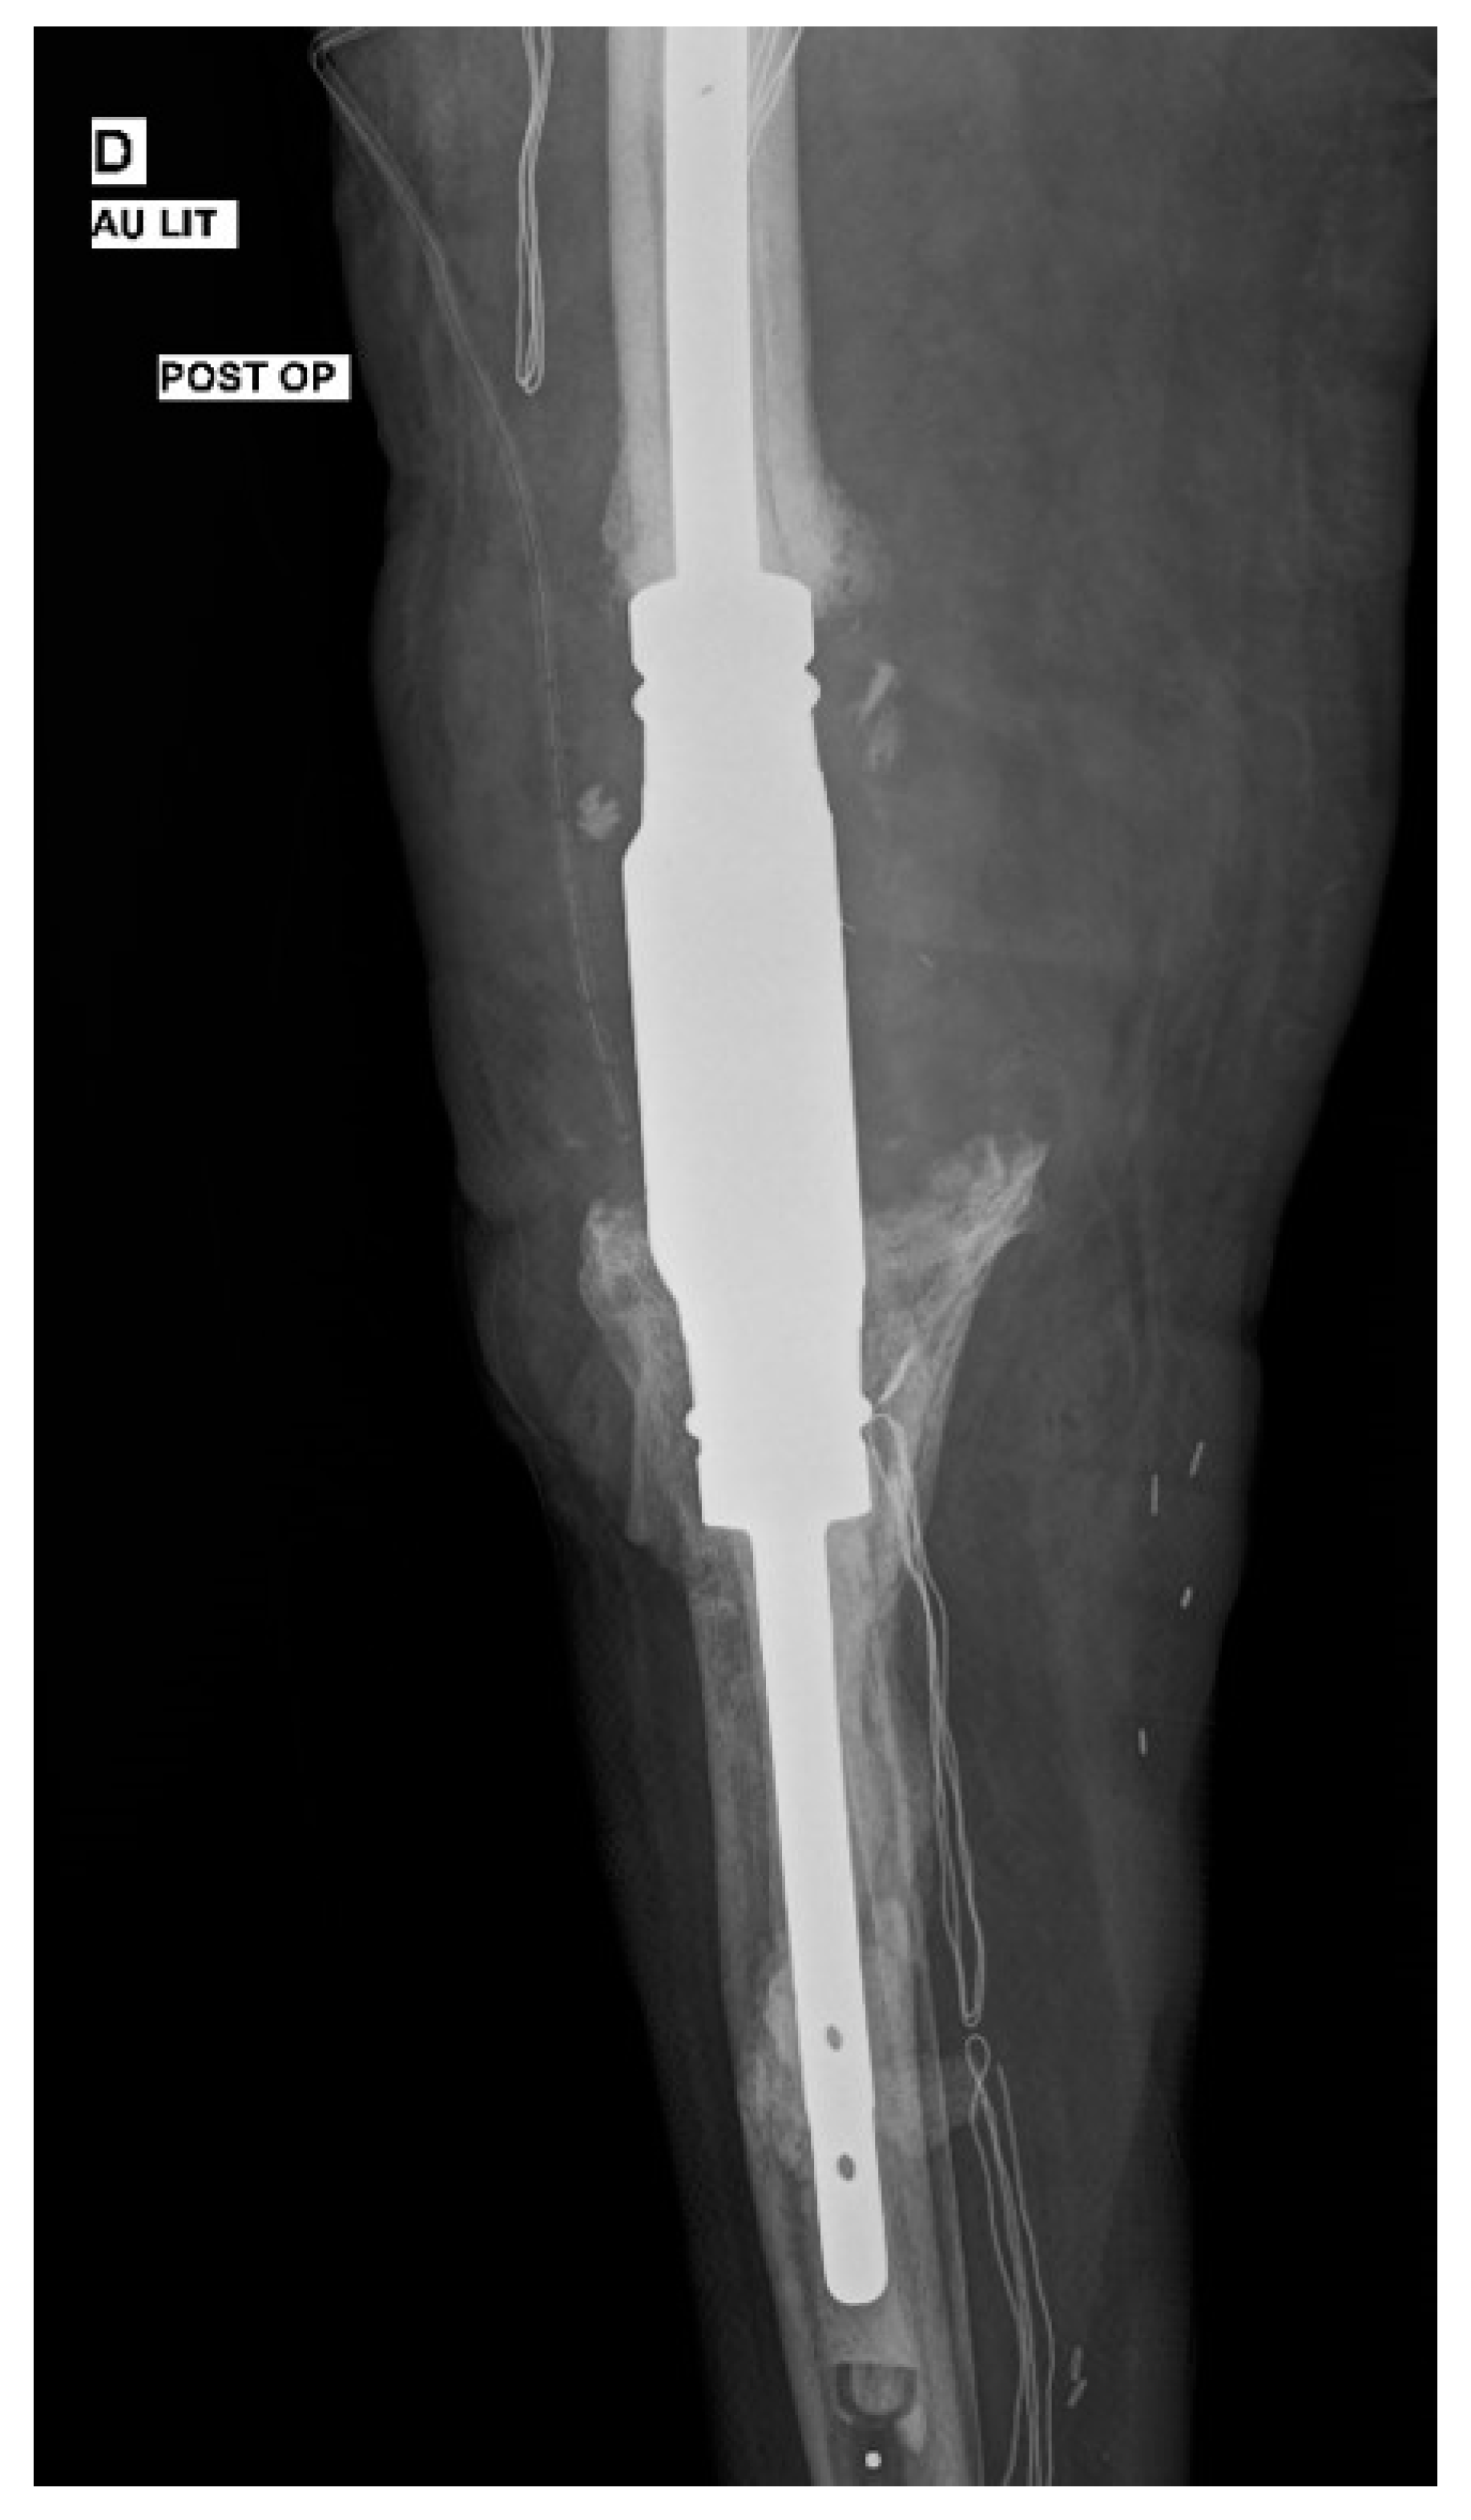

2. Case Presentation

| Present study, 2022 | Arthrodesis | - | Fluconazole | 4 | 4 | Success |